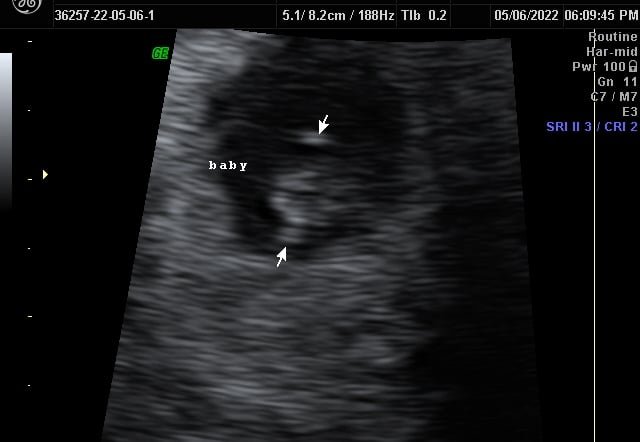

Our Gallery

Explore beautiful moments captured during our 3D and 4D sessions.